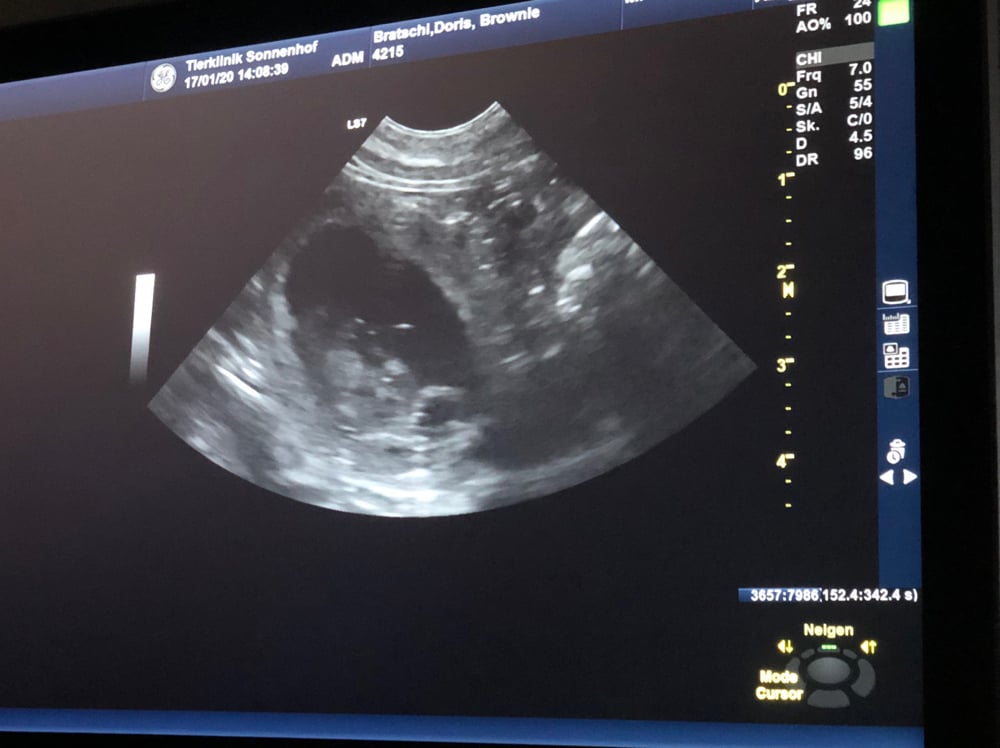

17.1.2020 Bei Brownie konnte die Trächtigkeit festgestellt werden allerdings gibt es nur 1 Welpe und dieser ist vorerst für mich reserviert- wirklich sehr sehr schade, dass es nicht mehr Welpen gibt aber die Natur es so entschieden......